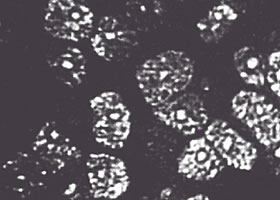

黒く見えているところが剥離部分で、多くの細胞が剥離してしまっているのが分かります。

ダメージを受けた角膜内内皮細胞